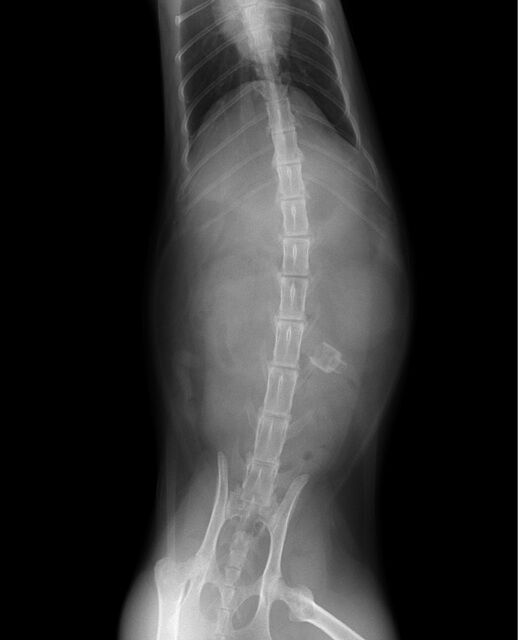

腸閉塞(ひも状異物) 松戸市・市川市 - かんじ動物病院